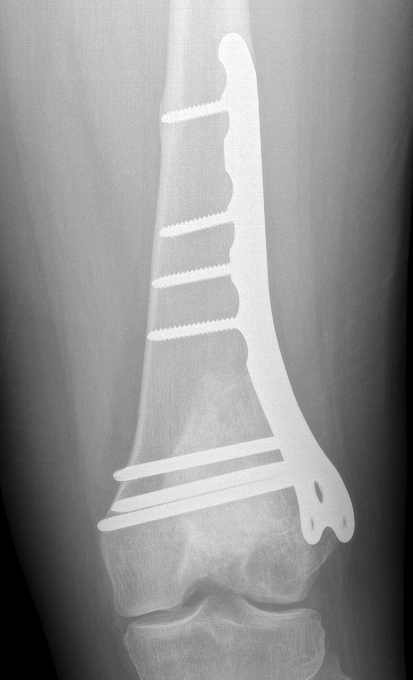

Currettage and Cement +/- local application phenol / liquid nitrogen

Technique

Open approach

- bone window

- remove tissue with curette

- saucerisation with high speed burr

- consider phenol / liquid nitrogen application

- cement (works by thermal necrosis), in addition to structural support

Results

- 354 GCT's treated surgically

- recurrence after curettage 18%

Knochentumoren et al JBJS Am 2008

- 384 cases

- recurrence significantly reduced by the use of cement